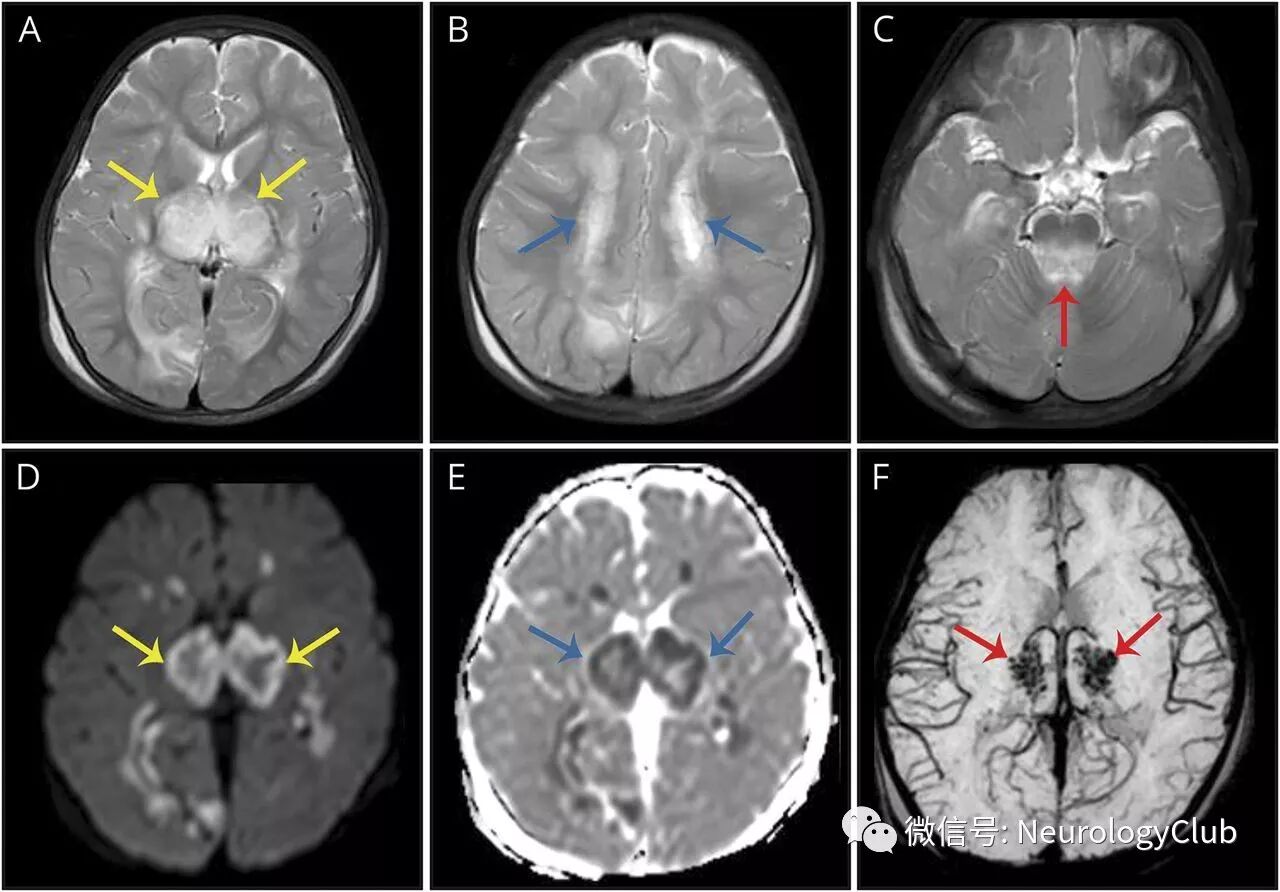

10月大婴儿,因癫痫持续状态就诊,2天前有发热和稀便。头颅MRI提示脑组织肿胀和累及丘脑,白质和背侧脑干的T2高信号病灶(图1)。丘脑病变在DWI和ADC上可见三层外观,伴有SWI上可见的局灶出血(图1-2)。

(图1:A-C:T2WI可见脑肿胀,丘脑、白质和背侧脑干高信号病灶;D-E:丘脑病灶在DWI和ADC上呈三层外观;F:SWI上可见丘脑病灶内局灶性点状出血)

(图2:ADC放大图;可见丘脑病灶三层结构;最里层为出血坏死,中间层为细胞毒性水肿,最外侧为血管源性水肿)